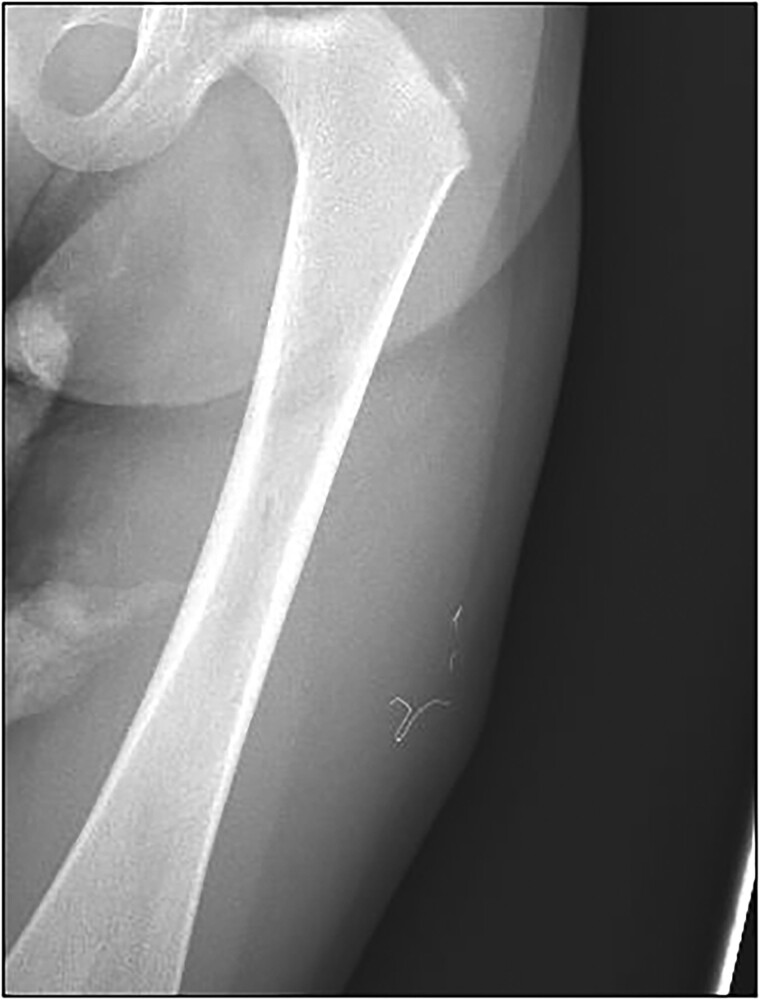

A 2-year-old male with genetic-negative, diazoxide-responsive hyperinsulinism presented with a knot in his left, lateral thigh. His hypoglycemia was managed with diazoxide, chlorothiazide, and monitoring via a Dexcom G6 continuous glucose monitor (CGM). X-ray showed 3 metallic wire foreign bodies, consistent with retained Dexcom sensor wires. He was referred to surgery for foreign body removal. Intraoperative fluoroscopy revealed 4 pieces of wire. Two superficial pieces were removed, but 2 small pieces deep to the fascia remained because of significant risk of injury or bleeding if removal was attempted. We present this case to increase awareness in the literature regarding retention of CGM wires. Raised nodules at sites of CGM insertion without fluctuation or erythema and persistent pain should raise suspicion for retention of sensor wires.

2岁男性,遗传阴性,二氮卓反应性高胰岛素症表现为左外侧大腿结。患者使用二氮氧化物、氯噻嗪治疗低血糖,并通过Dexcom G6连续血糖监测仪(CGM)进行监测。x线显示3个金属丝异物,与保留的Dexcom传感器丝一致。他被转到外科做异物取出手术。术中透视显示4根钢丝。两个表面的碎片被移除,但2个深至筋膜的小碎片仍然存在,因为如果试图移除,有很大的受伤或出血风险。我们提出这个病例是为了提高文献中对CGM金属丝潴留的认识。CGM插入部位隆起结节,无波动或红斑和持续疼痛,应怀疑传感器导线保留。